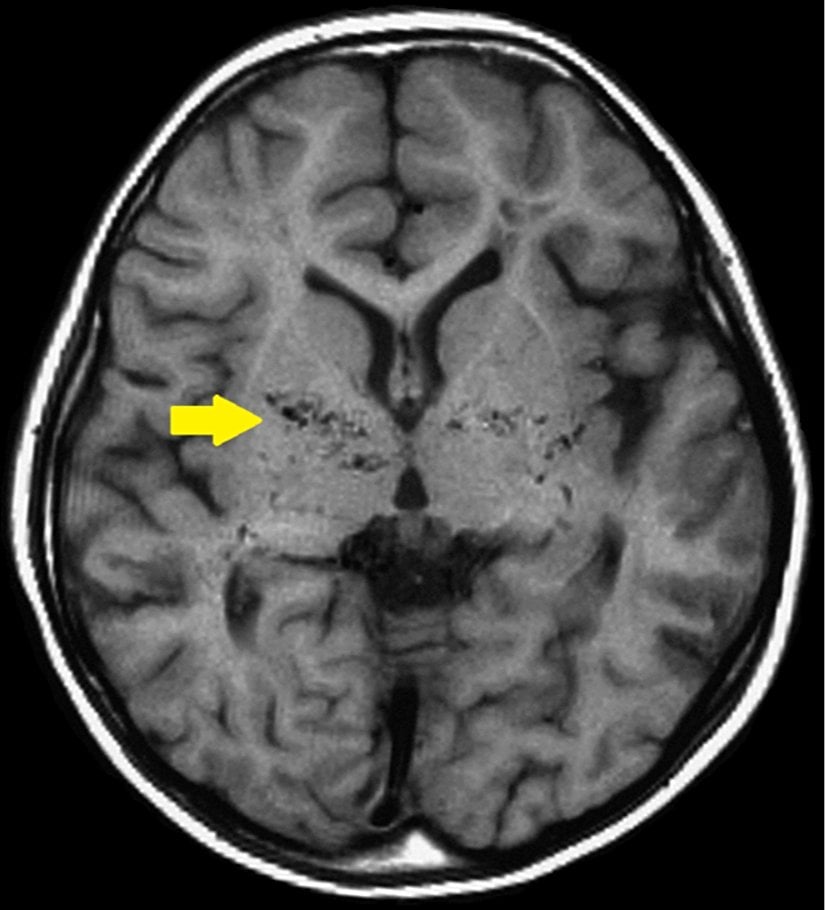

Moyamoya hastalığı; beyinde bulunan bazı arterlerin (damarların) daralması sonucunda ortaya çıkan kronik, ilerleyici bir serebrovasküler hastalıktır. Bu hastalık, Willis poligonunu oluşturan arterlerin bilateral, ilerleyici darlığı veya tıkanıklığına bağlı olarak gelişen kollateral damarların karakteristik bir özelliği olarak tanımlanır. Bu durum, beyne yeterli kan akışının sağlanamamasına ve oksijenin yetersiz olduğu bölgelerde iskemik semptomlara (kan eksikliğinden kaynaklanan belirtiler) yol açabilir. Hastalığın sebepleri net olarak bilinmemekle birlikte, genetik ve konjenital faktörlerin etkili olduğu düşünülmektedir. Ayrıca, bazı tümöral hastalıklarla birlikte görülebilir.[1], [2], [3], [4]

Tanıda etkili olan bir diğer unsur, hastanın klinik belirtileri ve görüntüleme bulgularıdır. Moyamoya hastalığının belirgin bulguları genellikle supraclinoid iç karotis arterleri ve bunların proksimal dallarını içerir.[7]